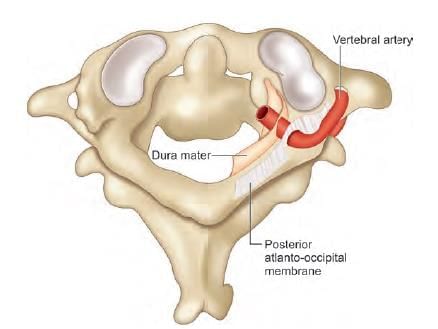

Third part of vertebral artery is related to which of the following marked region in the following diagram? (INI-CET Nov 2021)